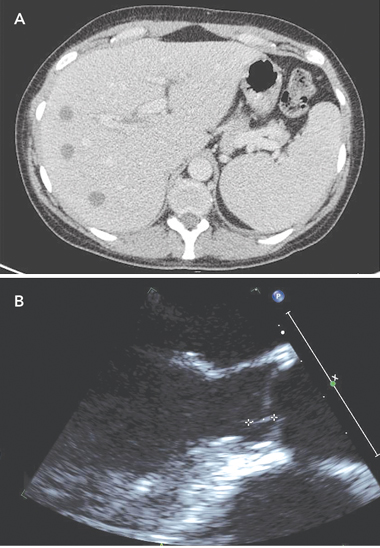

On Day 4, a computed tomography (CT) scan of the abdomen and pelvis showed multiple discrete hypodense lesions measuring up to 1.7 cm throughout the liver, and a bulky spleen (Box 1, A). Deep-purple and black colonies grew on Mueller–Hinton blood agar and antibiotic sensitivity plates. Chromobacterium violaceum, sensitive to ciprofloxacin, meropenem and co-trimoxazole, but resistant to gentamicin, was identified, and confirmed by testing on the VITEK 2 system (bioMérieux, Durham, NC, USA). B. pseudomallei, the causative organism of melioidosis,1 is not usually pigmented. The patient was commenced on intravenous meropenem.

Abatement of symptoms was slow, but the patient’s CRP level fell to 17 mg/L on Day 13. A repeat CT scan of the abdomen and pelvis on Day 10 showed generalised reduction in size of the liver abscesses. A transthoracic echocardiogram on Day 11 revealed mild mitral regurgitation. A contrast CT brain scan performed on Day 13 showed no abnormalities. A transoesophageal echocardiogram (TOE) performed on Day 15 demonstrated a small, 8 mm × 1 mm, linear mobile echodensity arising from the left ventricular outflow tract between the commissures of the left and right coronary cusps, consistent with a small vegetation (Box 1, B). An electrocardiogram was normal.